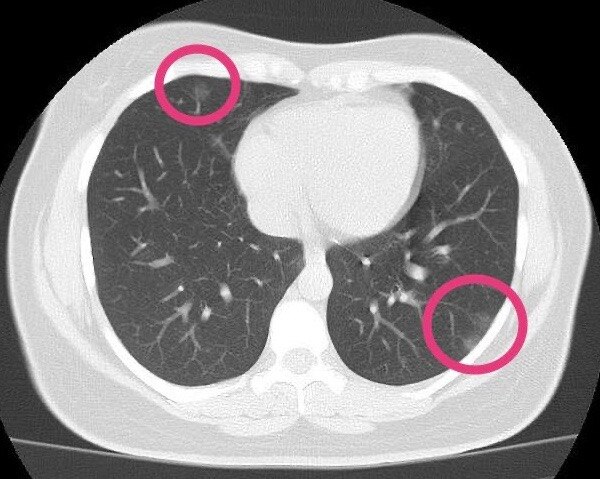

Ct Scans Of Coronavirus Patients Reveal Nature And Extent Of Lung Damage

The scan only takes a few minutes and is not painful. Ct scan showing a cancerous tumor in the left lung. How do ct scans work?